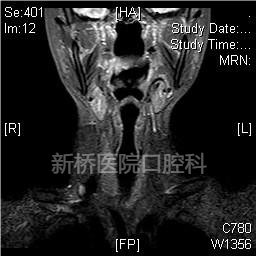

经口腔治疗口咽部、喉部、甚至咽下部区域的手术,因解剖结构复杂、视野严重受限,临床上操作难度极大。经口机器人手术(Transoral robotic surgeryTORS)是经口腔手术技术上的革新,属于内镜经口腔手术的一种。其利用带角度镜头臂伸入口内,使得上述部位放大的3D影像完整呈现于术者眼前,获得视野更宽广,更清晰,更逼真的深部